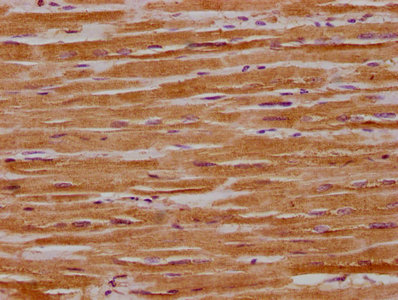

IHC image of CSB-PA016340HA01HU diluted at 1:300 and staining in paraffin-embedded human heart tissue performed on a Leica BondTM system. After dewaxing and hydration, antigen retrieval was mediated by high pressure in a citrate buffer (pH 6.0). Section was blocked with 10% normal goat serum 30min at RT. Then primary antibody (1% BSA) was incubated at 4°C overnight. The primary is detected by a biotinylated secondary antibody and visualized using an HRP conjugated SP system.